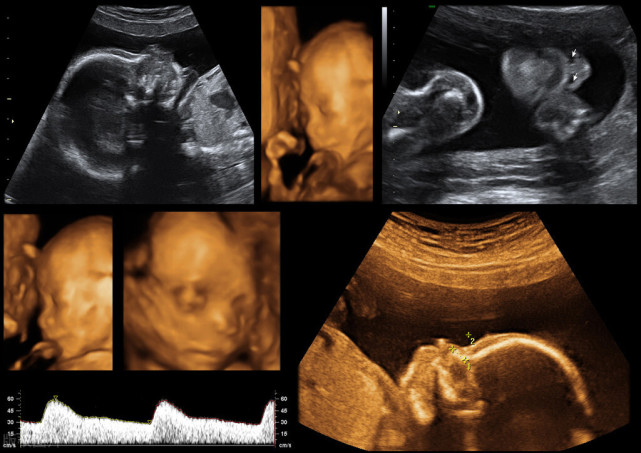

《孕前和孕期保健指南》建议孕妇在第三次孕检:20-24周时,进行系统超声筛查,就是我们俗称的“四维彩超”,大排畸筛查。

四维是高清动态的彩超,可以拍下胎儿的照片。但三维在筛查效果上,与四维并没有多大区别。

单胎建议孕24周做四维,双胎或多胎建议孕22周做四维。

四维不适宜过早或过晚做。过早做,胎儿小,看不清楚相关器官和肢体。太晚做,胎儿在体内长大了,不便于胎儿翻身让医生看到其他部位;同时,如果发现畸形,也耽误了治疗或处理的时间。

有些医院,建议孕32周再做一次大排畸。我当时产检的综合医院是只有一次大排畸,而妇幼医院是所有人都在孕24周、孕32周各开一次大排畸。

我们可以看到正常孕29-32周是建议做一次超声检查:查看胎儿生长发育情况、羊水量、胎位、胎盘位置等。一般如果医院建议孕32周再做一次四维,就可以替代这次超声检查,不需要再做一次B超了。

大排畸可以排除无脑儿、脑积水、肠道闭锁、肾积水、短肢畸形、部分先天性心脏病等。

但不能筛查:骨发育不良(需32周产科胎儿生长测量超声检查)、复杂心脏畸形、60%染色体疾病、智力、听力、视力的功能异常等。